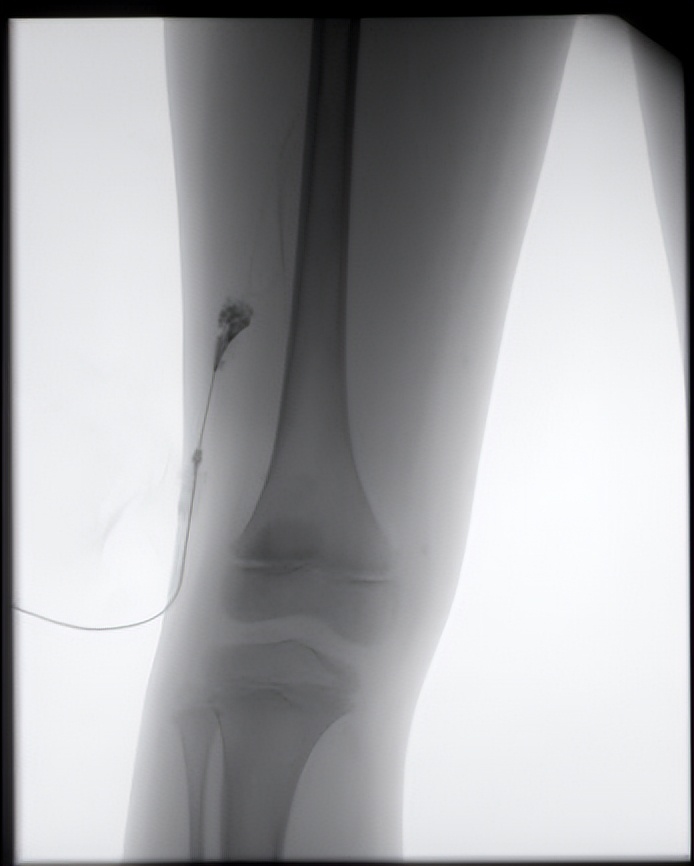

而且随着抽液,囊不见小!我团队人员立刻发觉这不是淋巴管瘤,随即,立刻为患儿做了造影,造影显示畸形静脉显影,引流静脉也显示出来,确定这是静脉畸形,然后按照静脉畸形的处理方式,经皮注射造影剂,确定是畸形的血管团后,局部注射硬化剂,注射硬化剂后局部皮肤略发白,使得血管内皮细胞破坏,从而达到治疗的目的。

术中造影